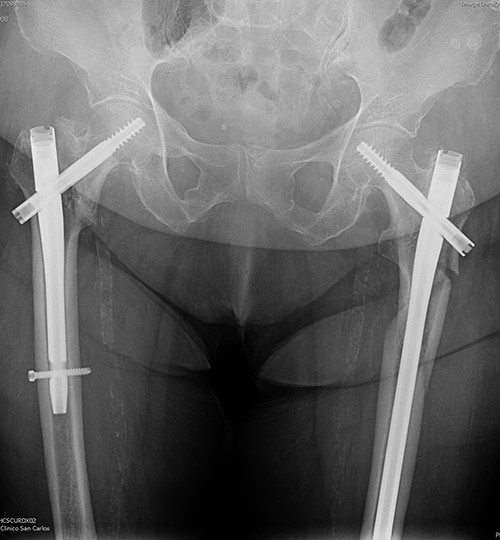

The postoperative course was satisfactory, without medical problems apart from non-complicated anemia (Hb 7.9 g/dl), solved with two units of red blood. On the first postoperative day, a radiographic control was completed (Fig. 3) and started early ambulation assisted by physiotherapists. On day twelve, she was transferred to a rehabilitation hospital. Outpatient follow-up visits evolving reasonably well. In the 6-month and 1-year check-up, the consolidation of the fracture was observed in the radiographic study (Fig. 4). No surgical wound problems, infections, or limping were identified. Anti-osteoporotic drug treatment was implemented along with an emphasis on a healthy diet with adequate protein intake and supplementation with calcium and vitamin D.

Radiological evaluation on follow-up at 1 year. Pelvis anteroposterior radiograph view showing signs of consolidation, without evidence of loss of reduction or implant failure.